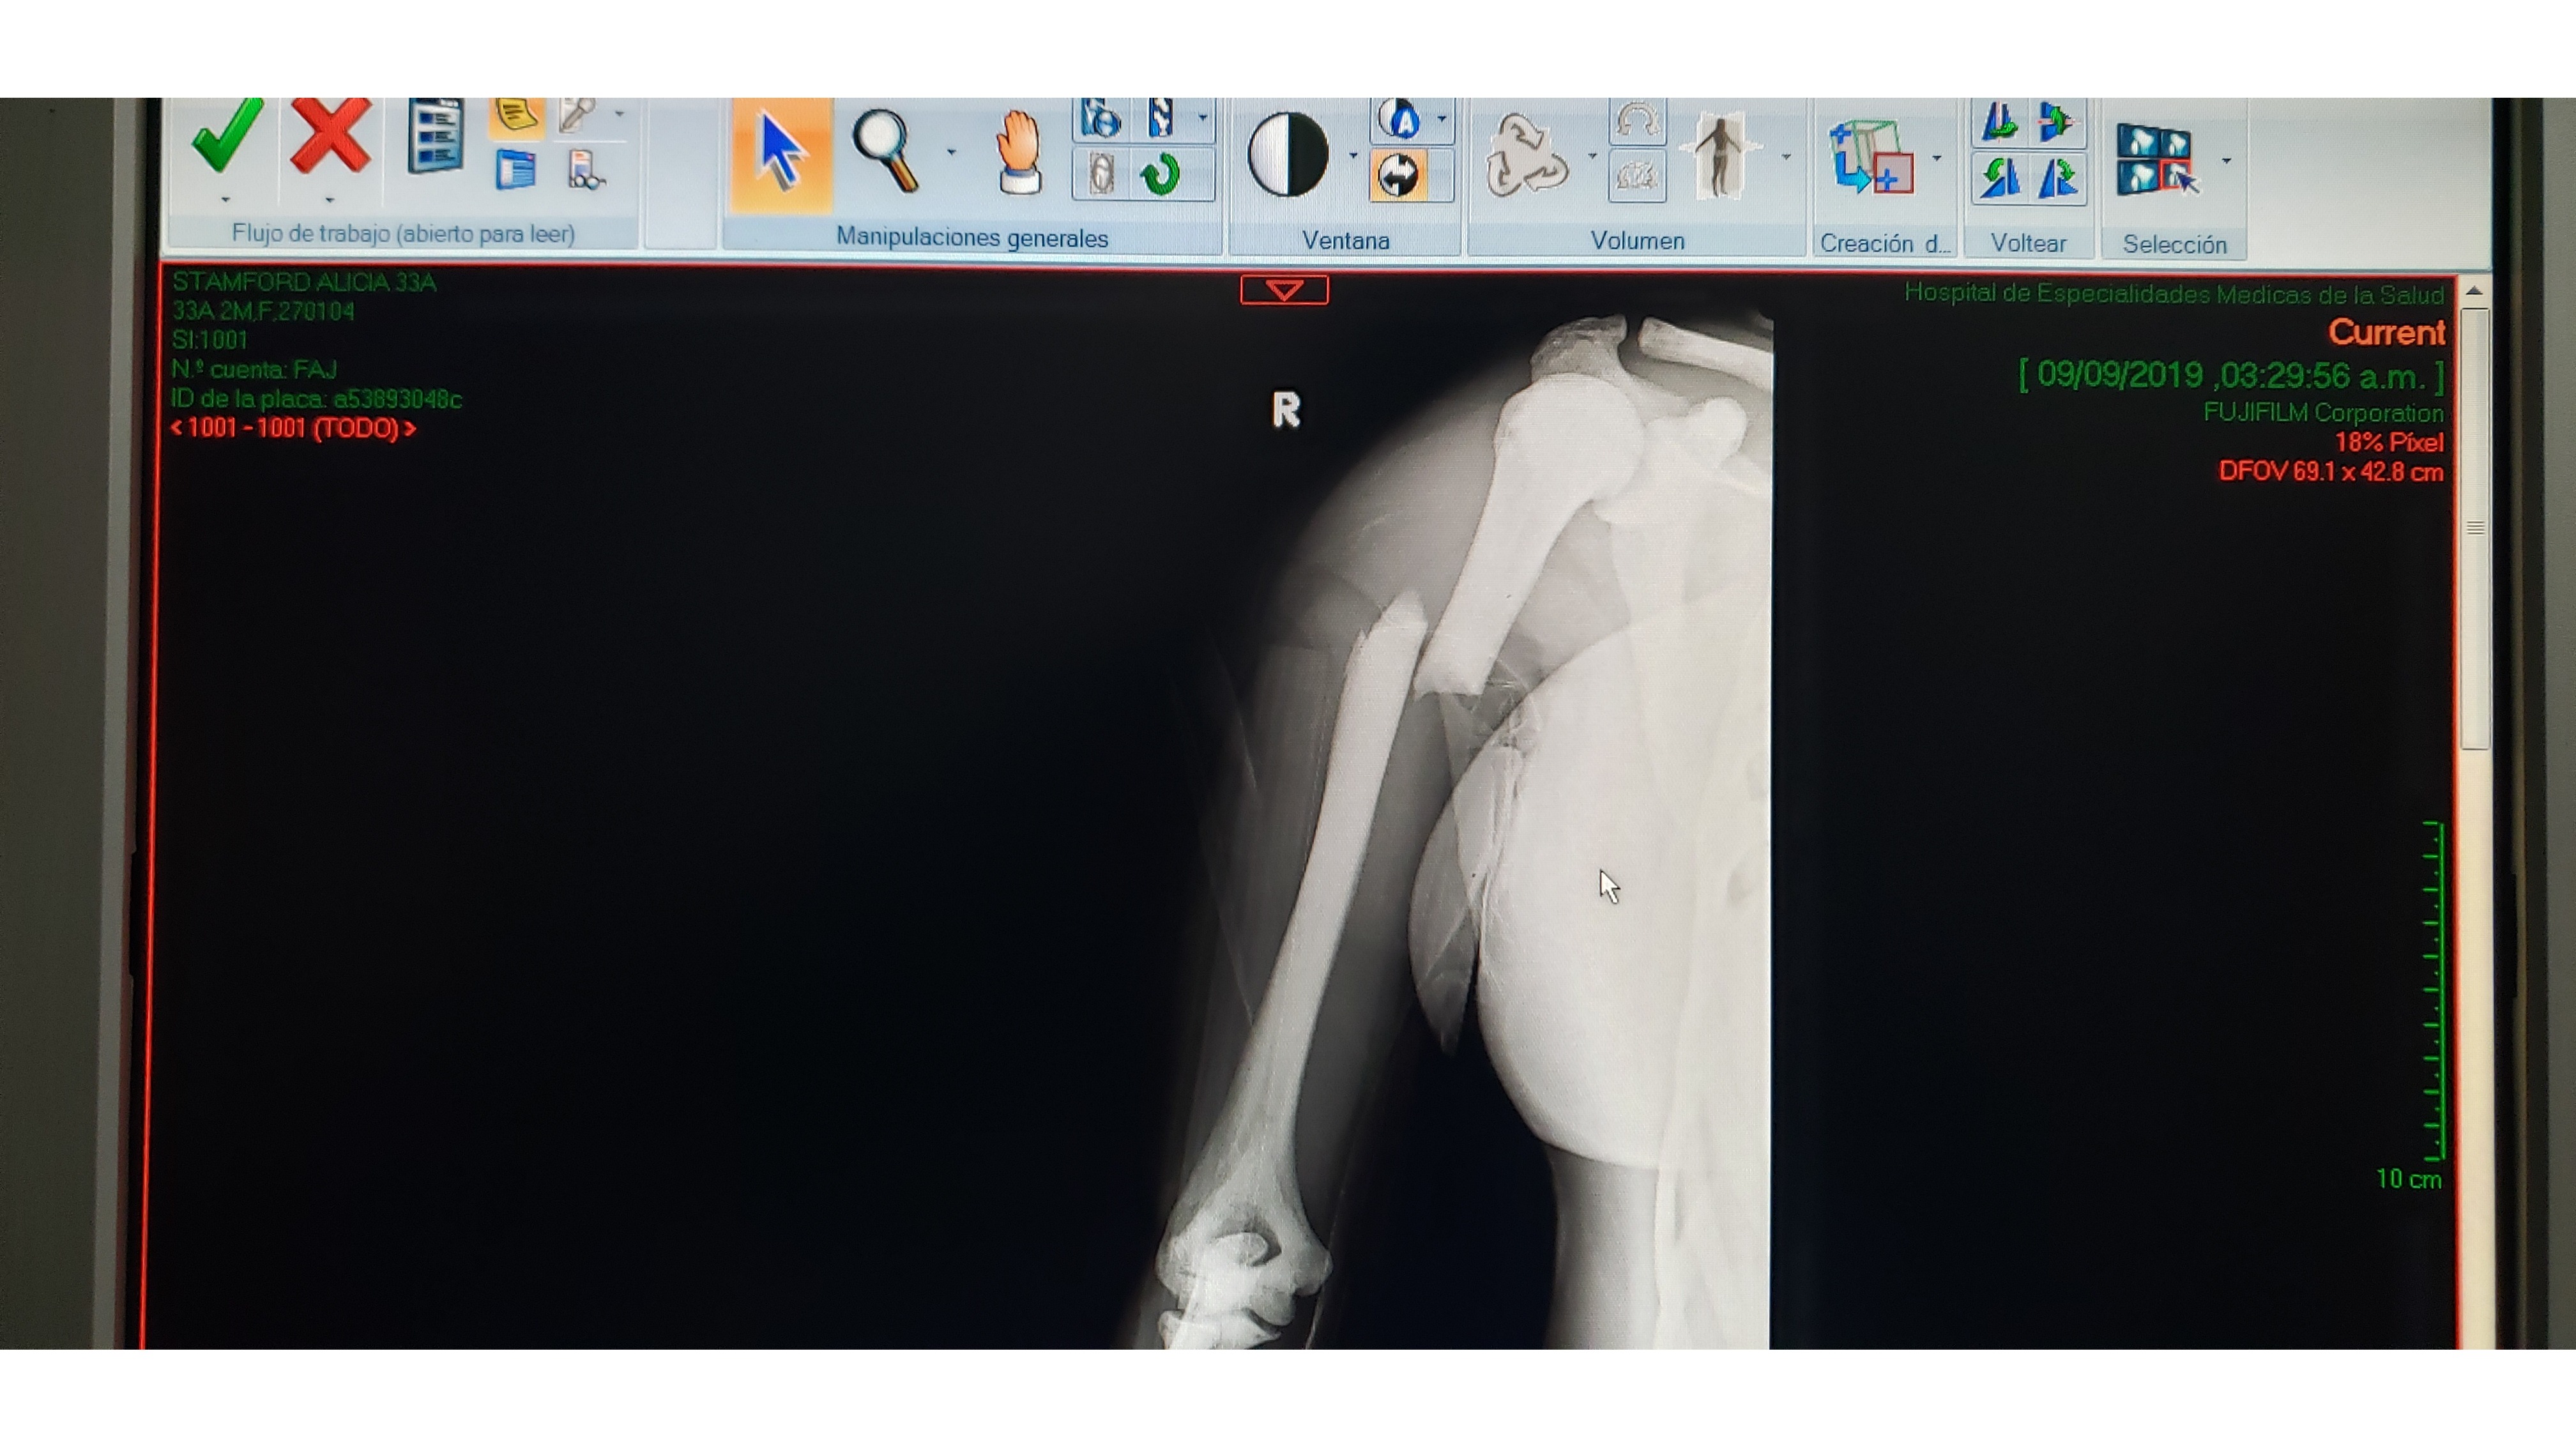

Please help me in supporting my dear friend Alicia who is currently going through the toughest time of her life, both physically and emotionally. ABOUT ALICIA Alicia is a 33 year old Australian, full of life and loves adventure. It had long been Alicia’s dream to travel overseas to Latin America. She saved for years, and set off in 2018. She fell in love with Mexico before she could move on to her next destination, and soon found her calling: to become a Divemaster or English teacher. Alicia fell off her bicycle last year and damaged her elbow, dashing her hopes of moving on to become a dive instructor. This was one of the worst hospital experiences she has ever had to endure, until last week. THE ACCIDENT Just over a week ago, Alicia was hiking with friends in the Sierra Alvarez in San Luis Potosí, in the centre of Mexico. Alicia had a bad fall and her leg and arm were pinned to the ground. The group was out of cell range and the guide had brought no first aid kit. She was made to believe there was nothing wrong and to move herself into sitting position and work her way out of shock. After two hours of trying to move her, the group dispersed to try to find help. They returned with a rescue crew 6 hours later, by this time it was dark and Alicia was beginning to suffer from, hypothermia and dehydration. The rescue team had to hike with Alicia tied to a table and transport her on the back of a truck on a 4x4 track then transfer her to an ambulance. To top if off, the ambulance had an accident by colliding with a tree trunk trying to get through the dark remote area, causing Alicia even more pain on the 2 hour drive back to the city. The rescue operation took 6 hours, all without anesthesia. THE HOSPITAL When she finally made it to the hospital, she was advised that she had fractured her femur in 3 places and had also fractured her upper arm on the opposite side. She woke up from her first operation to hear that it had been unsuccessful. She lost a lot of blood during the operation and we almost lost her. She was in ICU for several days. Upon waking from her second operation, Alicia was given the devastating news that her mother (who had been gravely ill) had passed away. The hospital had claimed they would work directly with her travel insurance at the beginning so they could admit her, and then took back their promise right before the operation. Every day whilst Alicia was in ICU, the hospital came collecting money, which Alicia's loving partner Chris had to borrow from everyone he knew to pay so they would not kick her onto the street. WHAT'S NEXT? We can only imagine the physical and emotional pain that Alicia has been going through – she has lost her independence, mobility and ability to make a living at the same time as she is grieving for the loss of her mother. She now faces an uphill battle – physically, emotionally and financially. Although she has now been released from hospital, Alicia will not be able to leave her bed for the next 2 months whilst her leg heals. She is unable to move independently and is fully reliant on help to feed, dress and shower her. Luckily, she is being cared for by Chris and his family. Once the two months are up, she has to leave Mexico and return Australia as soon as she is able to complete her medical recovery there. Alicia will have to return to Australia without her partner with no idea of if he will be able to join her in the future. She faces an uncertain future and has no idea when she will be able to work to support herself again. What's worse, she now no longer has the support of her mother to help her through this time. HOW YOU CAN HELP On her return to Australia, she will have to start afresh and will need funds to help support herself until she is well enough to find work again. She will need months of physiotherapy and counselling, lots of medications which all add up, plus taxis to get to all of her medical appointments, plus food and rent whilst she is not working. I know that Alicia is extremely uncomfortable about asking for financial help, but I asked her to swallow her pride. When bad things happen to other people, we often ask ‘what can we do to help?’ It’s especially hard to feel useful when someone is suffering miles away on the other side of the world. Making a small donation to help Alicia get through these next months would mean the world to her. She is going to have a tough enough time getting through the physical pain she is experiencing, let alone the grief she is feeling for having lost her mother, the sadness she feels at having to leave Chris and Mexico, and her uncertainty about her future in Australia. Being so far away, we can't offer her any physical help, but it doesn't take much to pull a credit card and give a few dollars, those dollars will mean more to her than whatever you may spend it on later this week. This is ‘what you can do to help’ to show Alicia that you support and love her during this extremely difficult time. Thank you xx Image 1: Alicia on her travels Image 2: The last time Alicia saw her mother, saying goodbye in Australia. Image 3: Alicia with her loving partner Chris, who unfortunately can't join her in Australia for financial reasons. Image 4: Alicia broke her femur in 3 places and is set for month of painful therapy before she can walk. Image 5: Alicia's humerus bone was highly displaced.